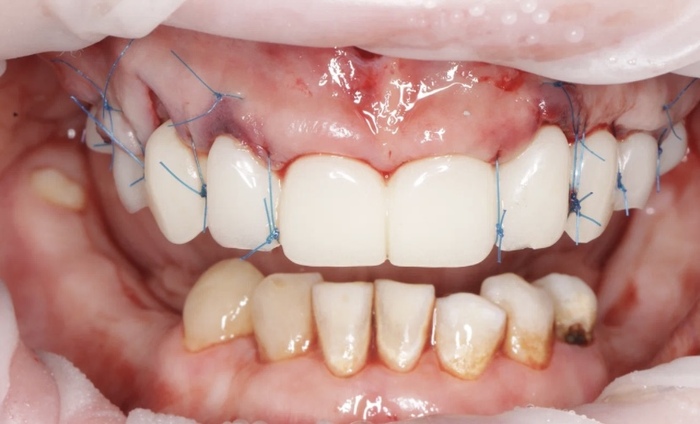

И вот то что со мной делали 7 часов злые тети врачи:

Кстати не все прошло так гладко, у меня порвался синус во время операции и я спала 7 часов а не 5. В этот раз я оочень тяжело отходила от сна. Было очень плохо, я была как овоща еще сутки . Боль пришла на сл вечер, вот то что я говорила больно удалять сразу много зубов больно-фигня. Я познала боль когда мне удалили остальные верхние и вкрутили титан в кости. Я выла без обезбола, я хотела биться головой об стену, нос течет водой, голова болит и рот не открывается и в зеркале я видела Олега монгола , опять. Питание ТОЛЬКО жидкое. 3 месяца. Через 3 месяца мне поставят постоянные. На данном этапе я хожу с пластиком чтобы десна зажили именно под форму будущих зубов . Из хорошего: я уже привыкла к новым ощущениям во рту, у меня оказывается есть скулы 😳, и я вернула внешность уже, ту которая была до спиливания зубов .

Вот так меня фоткали для отчета. Это моя безупречная улыбка за день 😀 не судите строго, мне сказали сделать такой оскал )

И барабанная дробь!!! Это сразу после операции))